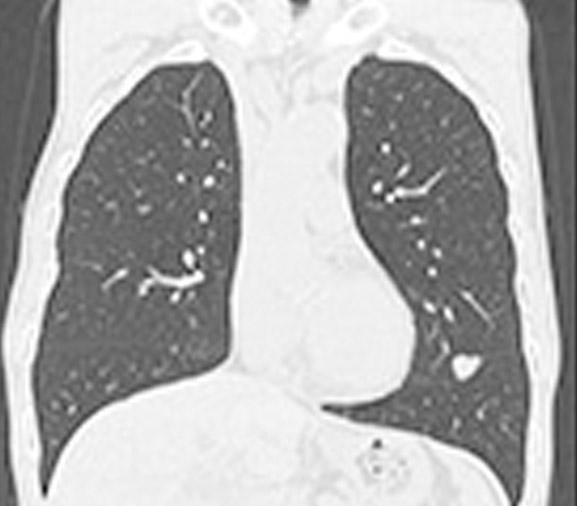

新病院移転と共に、80列マルチスライスCTを導入しました。以前の装置より広範囲をより速く撮影する事ができ、胸部撮影で約5秒、腹部撮影で約10秒の息止めにて撮影出来ます。また、最新の画像処理により以前より少ない被ばく線量にて検査を受ける事が出来るようになりました。

細かいスライスで撮影するため小さな結石でも容易に発見ができ、正確な位置情報を診断する事が出来ます。

従来の輪切りの画像だけではなく、さまざまな方向からの断面像や画像解析装置による診断に有効な3D(立体)表示をして臓器(主に腎臓・前立腺・膀胱)や病巣の大きさ・形状を把握する事が出来ます。造影剤を使用しながら撮影する事により、より鮮明な画像が得られます。